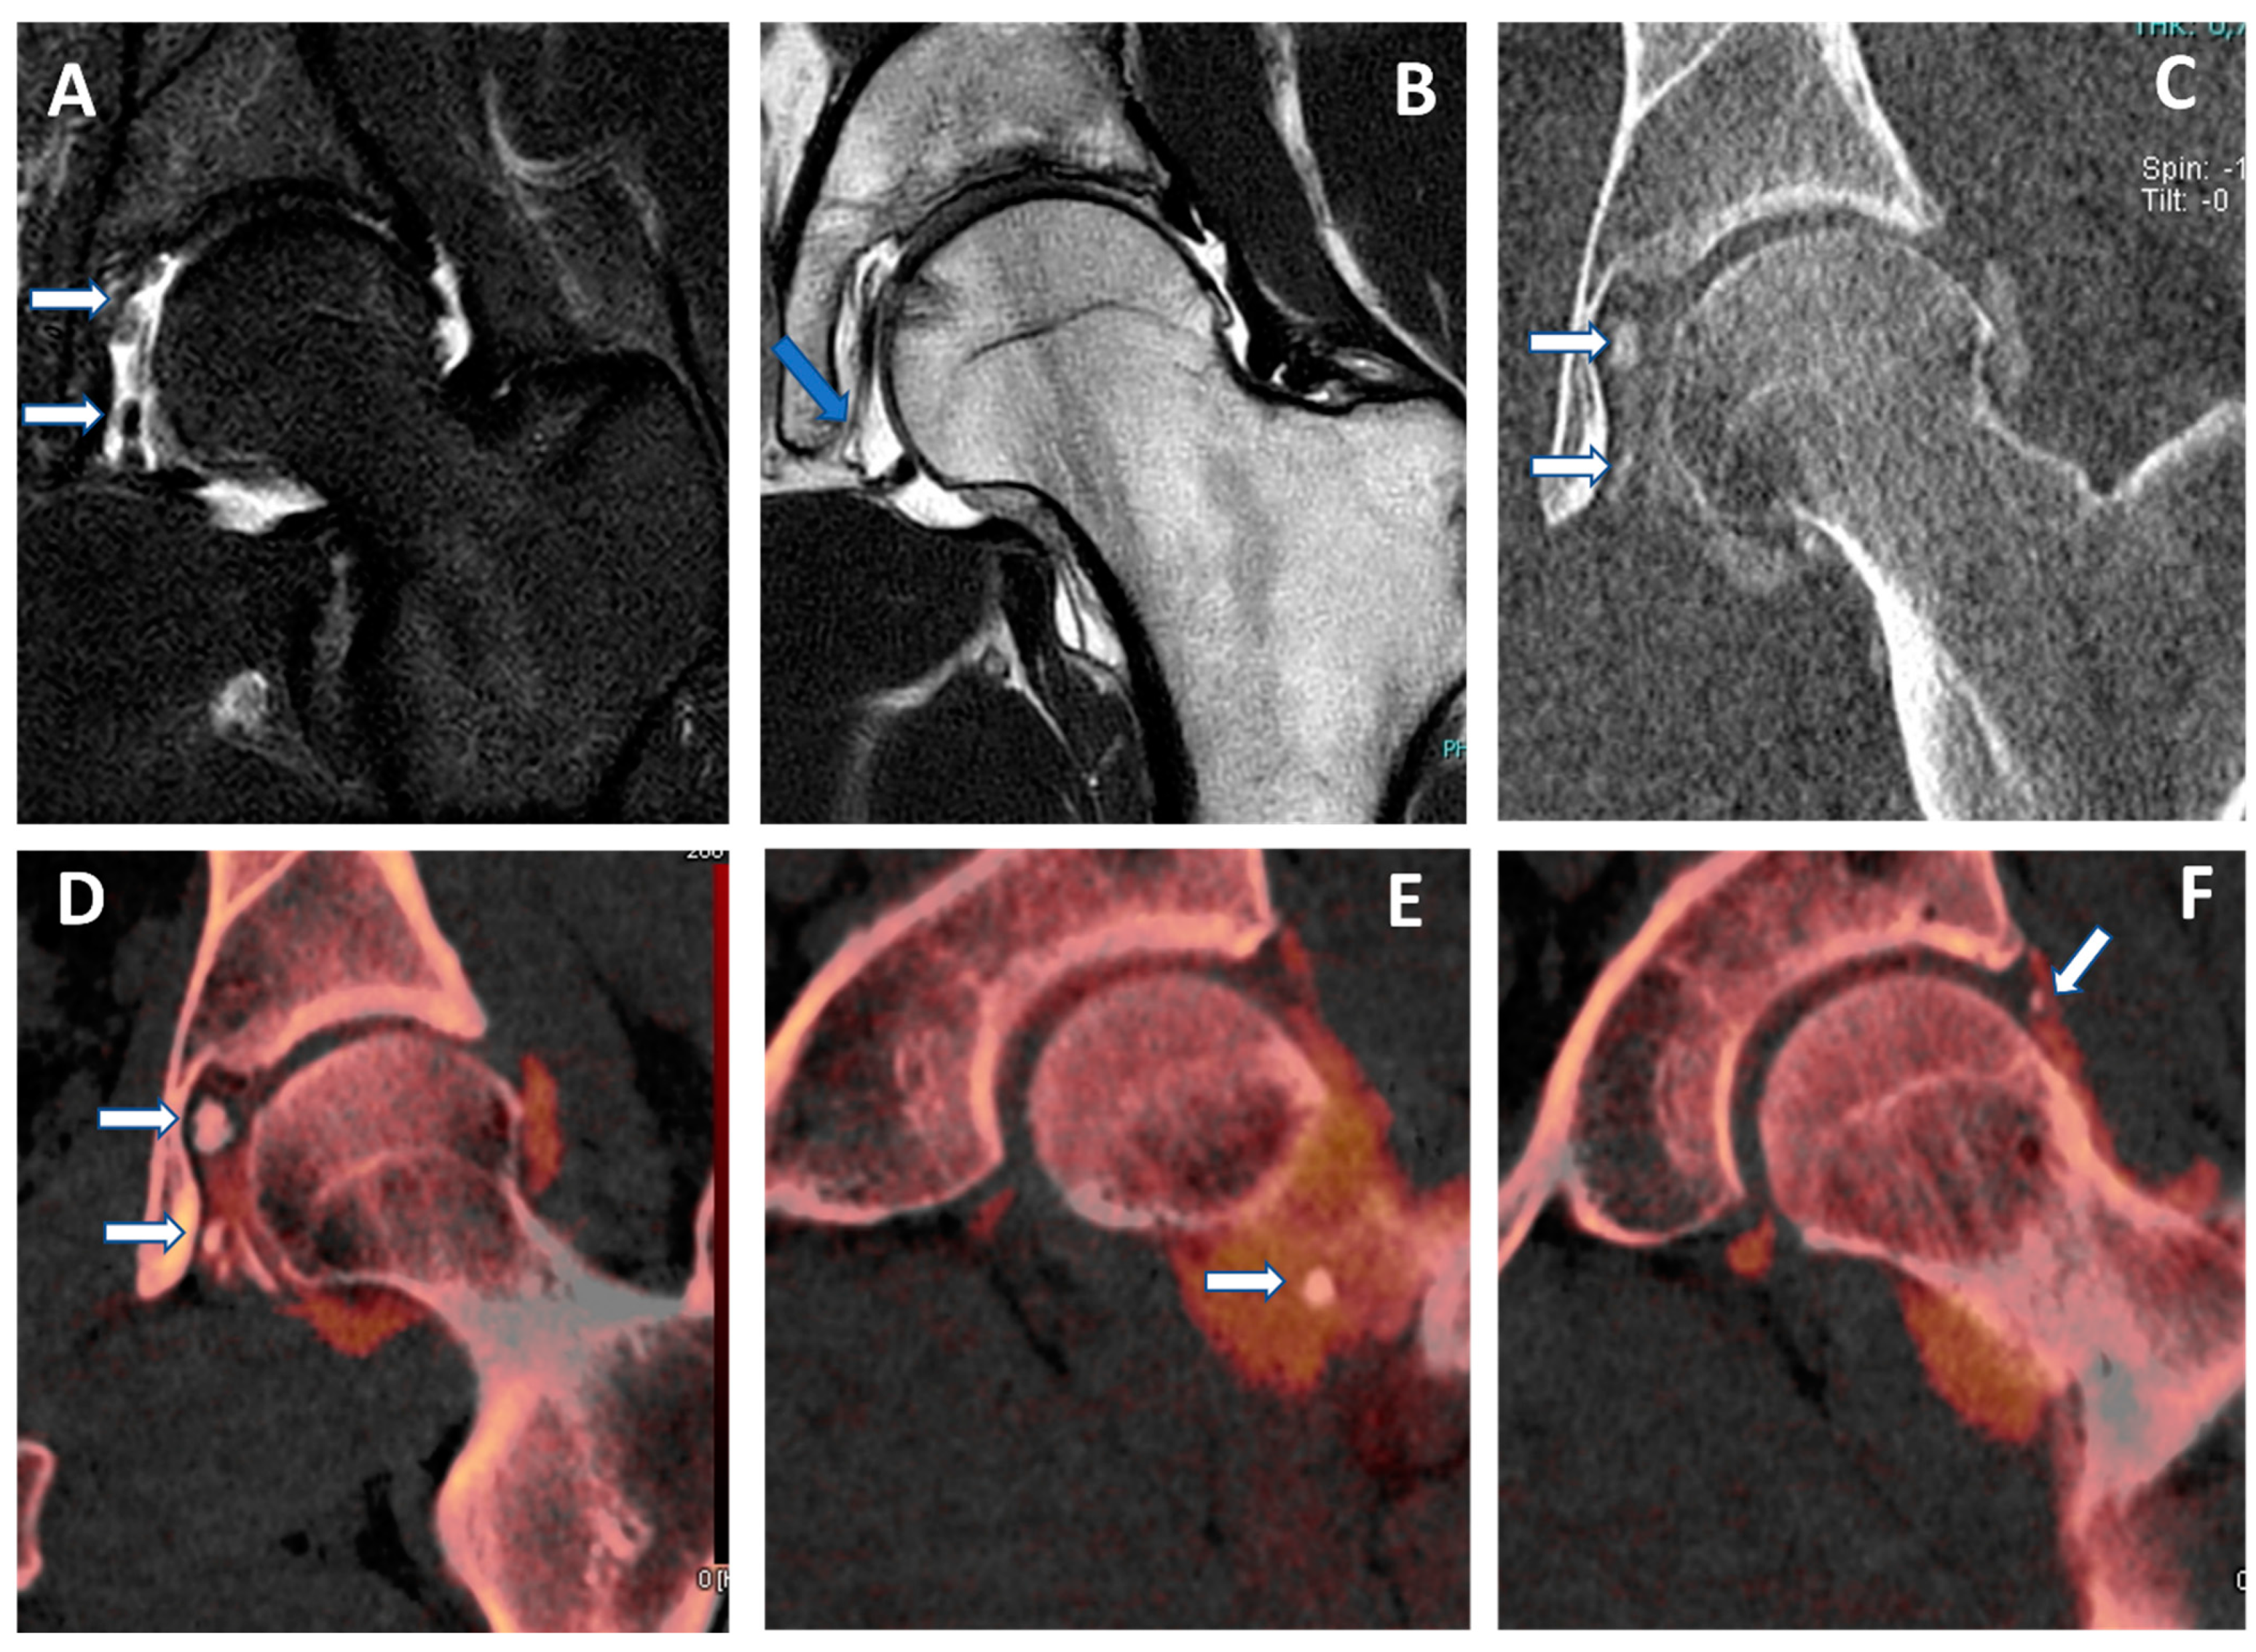

Figure 5. Capsular, labral, and loose calcifications in femoro-acetabular impingement. On MRA coronal STIR and T1 weighted images (A,B), it is possible to recognize subtle filling defects (arrows on (A)) and capsular thickening (blue arrow in (B)). On the DECTA VMI 1 mm coronal reconstructed image (C), calcifications are partially and erroneously subtracted (arrows). The corresponding DECTA iodine map images (DF), reconstructed on the coronal plane (1 mm thickness), clearly show the presence of loose bodies and capsular and labral calcifications (arrows).